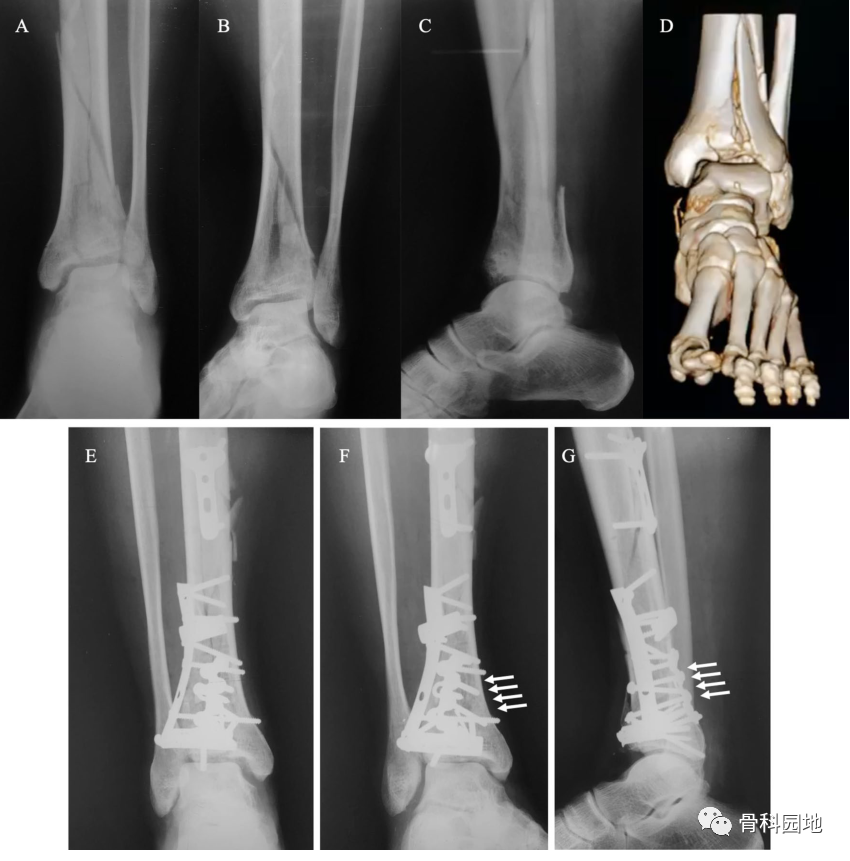

六、pilon骨折

后踝骨折应用直跟骨板(箭头)